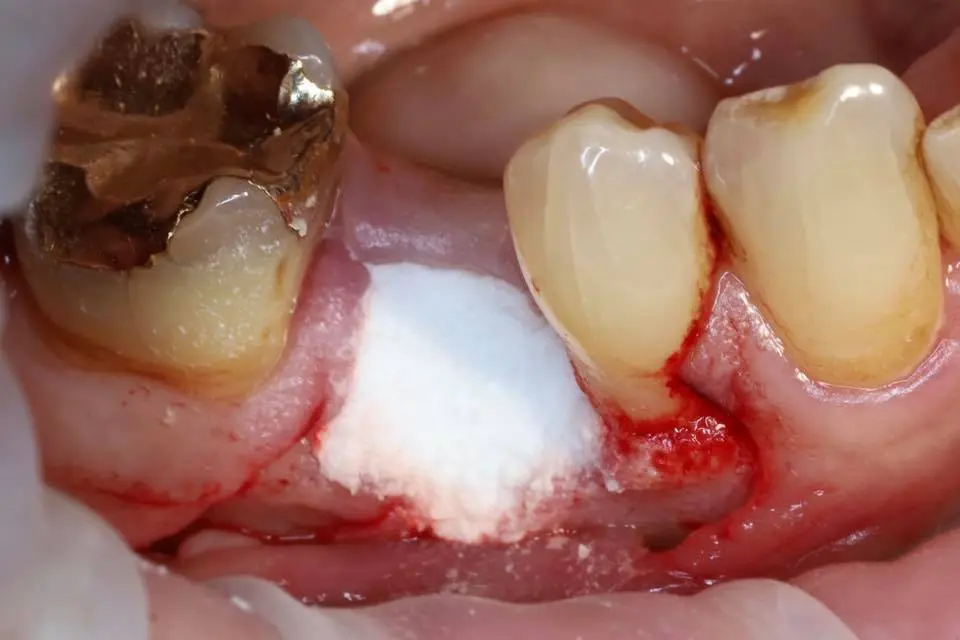

Seminaariesitykset keskittyvät täysin synteettiseen EthOss-biomateriaaliin, joka on kehitetty edistämään potilaan omaa luun uudistumista hammasimplanttien ja suukirurgian yhteydessä. EthOss koostuu β-trikalsiumfosfaatista ja kalsiumsulfaatista, jotka luovat ihanteelliset olosuhteet luun kasvulle ilman sulamattomia vieraspartikkeleita tai eläinperäisiä aineita, korvautuen kokonaan elävällä isäntäluulla noin 6–12 kuukaudessa.

Esityksissä käsitellään materiaalin valmistelua, käyttöä luusiirteissä sekä kliinisiä tuloksia, kuten nopeaa luunmuodostusta (jopa 50 % uutta luuta 12 viikossa), ilman tarvetta erilliselle kollageenikalvolle.

This lecture will explore how surgical simplicity combined with biologically active materials can achieve outstanding results across a range of indications — from socket preservation and regeneration to sinus lifting. Through clinical cases and practical protocols, Dr. Stuart Kilner will demonstrate how to optimise handling, improve efficiency, and achieve stable regeneration by working with, not against, the body’s innate capacity to heal.

EthOss cases by Dr Stuart Kilner